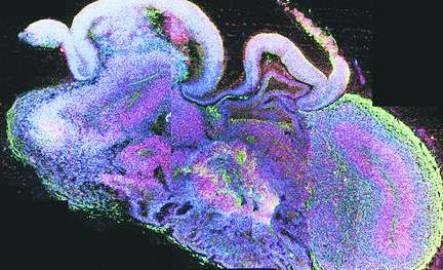

Sección cruzada completa de un mini cerebro que muestra el desarrollo de las regiones del cerebro.Madeline A. Lancaster

El método, explicado en el último número de Nature, permite que las células madre pluripotentes se conviertan en órganos cerebrales -o 'mini cerebros'- cuyo desarrollo ha conducido a la formación de regiones cerebrales independientes.

El órgano resultante fue un tejido continuo que rodeaba una cavidad llena de fluido que era una reminiscencia de un ventrículo cerebral. Al cabo de unos 20 o 30 días se desarrollaron regiones cerebrales definidas: córtex cerebral, retina, meninges y el plexo coroideo.